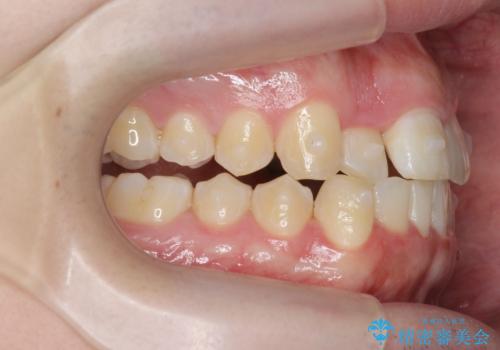

前歯が隠れていて見えない クロスバイトの矯正治療

- 「前歯が1本隠れていて見えない、歯並びを矯正治療で改善したい。」と希望され来院されました。

奥に隠れている前歯を並べられるスペースを確保したのち、歯並びを整えていきます。

前歯のスペース不足により1本だけ後方に位置している状態でしたが、しっかりとスペースを確保し配列することができました。